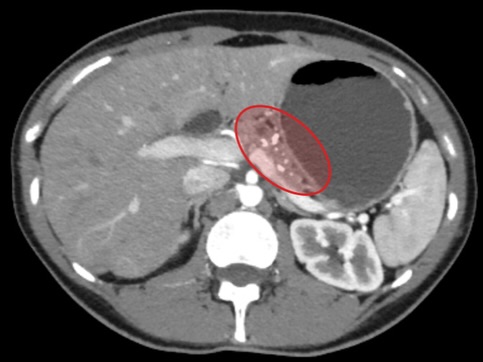

Під час нещодавнього планового обстеження медики виявили несподівану патологію — каміння у підшлунковій залозі, що є вкрай рідкісним і небезпечним станом. Таке захворювання може призвести до гострого панкреатиту або механічної жовтяниці через порушення відтоку жовчі та панкреатичних соків.

Ірині виконали мініінвазивну лапароскопічну операцію Фрея, під час якої видалили конкременти, очистили протоки та частково висікли уражені тканини підшлункової залози. Втручання пройшло успішно та забезпечило швидке відновлення.